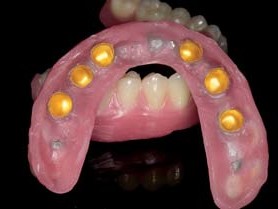

Fertigstellung der Konusprothesen

Mit entsprechenden Einbringhilfen zur exakten Ausrichtung verschraubte der Zahnarzt die individuellen Abutments mit den Implantaten und zementierte darauf die Patrizen aus Zirkonoxid. Setzt man dazu bereits die Galvanokappen auf, lassen sich die Zementüberschüsse einfacher und ohne Beschädigung der hochglanzpolierten Zirkonoxidoberflächen der Primärstruktur entfernen. Anschließend wurde das Tertiärgerüst intraoral nach dem Weigl-Protokoll im passiv fit mit den Galvanosekundärteilen verklebt. Für die folgende Ästhetikeinprobe wurden die Prothesenzähne in Wachs auf dem Gerüst aufgestellt. Das Gerüst wurde opakert und darauf die hohlgeschliffenen Prothesenzähne unter ständiger Kontrolle am Vorwall einpolymerisiert. Nach dem Finishing der Prothese konnte die Versorgung eingesetzt werden, eine okklusale Adjustierung war aufgrund der exakten Kiefer relationsbestimmung nicht notwendig (Abb. 24–30).